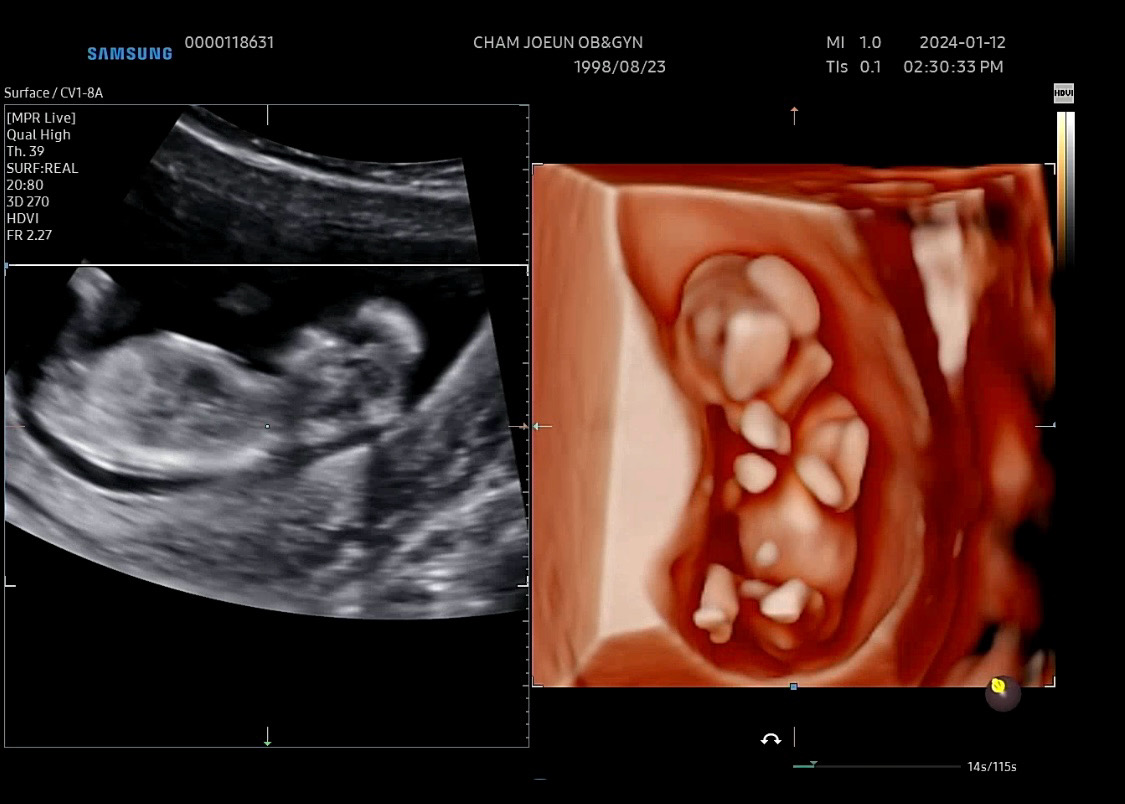

12주차 성별

오늘 1차 기형아검사 끝냈구 밑에 알 두개가 보이는데 ... 의 사 쌤도 모르겠다고 한달 뒤에 보자고 하더라구요 ㅠㅠ 주위에서 다 아들 같다고 하긴 하는데 딸 3명 있는 지인은 또 딸 같다고 말해서 ... ㅠㅠ 여러분들이 보시기엔 어떤가요 !?!